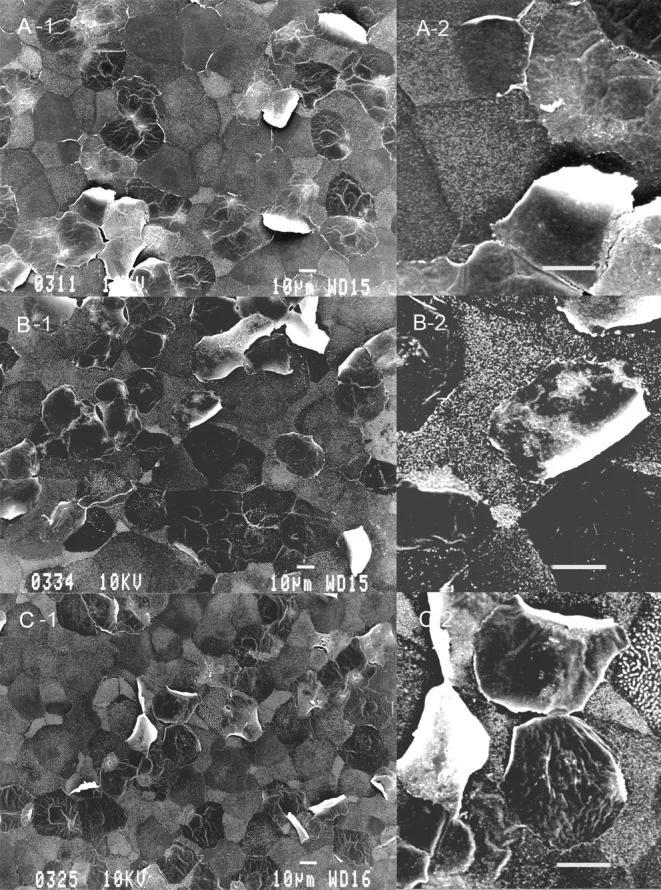

苯扎氯銨(BAK)對角膜上皮細胞造成損傷的掃描電子顯微鏡(SEM)圖像

最上(對照組/正常):展示的是健康的角膜上皮。

中圖(初步受損):接觸低濃度苯扎氯銨後,原本平整的表面開始變得不再規則。

下圖(嚴重受損):接觸高濃度或長期使用後,細胞膜被大面積破壞。